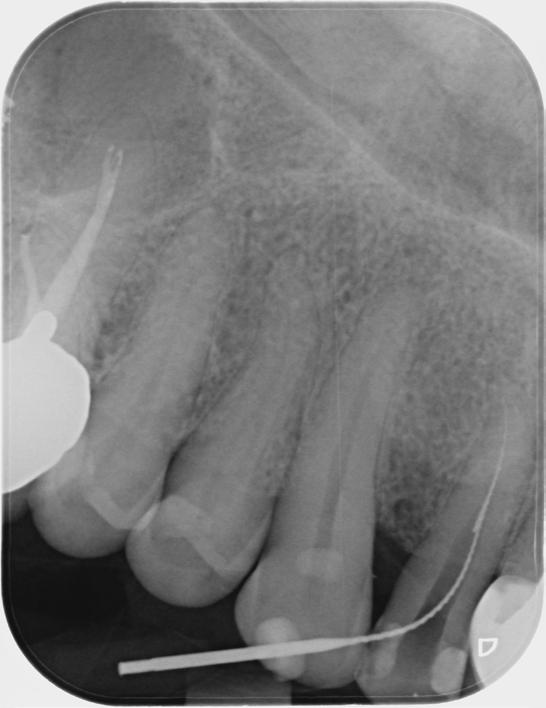

Based on the clinical and radiographic findings, tooth 22 was diagnosed as necrotic with a possibly infected root canal system (RCS), pulp canal calcification and primary acute apical periodontitis due to decay, cracks and restoration breaking down. An endodontic investigation procedure was planned to determine whether the 22 was suitable for further restoration. While the treatment was supposed to be straightforward initially, it progressed to become very complex surprisingly. This was due to separation of a size-10 H-file in the root canal of tooth 22.

The instrument separation was first noticed after taking the initial radiograph to establish the working length. It probably happened due to the patient biting inadvertently on the file during x-ray exposure. As our patient was a bruxer, his bite forced the file deeper in the

severely calcified root canal. The file was now firmly stuck inside the root canal. Despite trying to gently retrieve the file, it broke at junction of the cutting surface to the shank. Bypassing and/or retrieval procedures were planned and performed by using hand files, rotary files and Satelec ultrasonic tips in three different sessions, each one almost three hours long. Rotary files were used mainly as adjunctive instruments.

Taking advantage of rotary files made of a heat-treated alloy with minimal cutting efficiency, designed in a way to scrape rather than cut the dentin, enabled me to safely enlarge the space made by the hand files. This technique also participated in less frequency and chance of breaking more files next to the broken file.

Finally, the broken file segment was removed with braiding barbed broaches around the file. Notably, the patient patiently cooperated all throughout the treatment.

I had a thorough discussion with the patient about the reasons why this incident happened. Even though I could have simply pointed out a severely calcified root canal or a heavy bite to be responsible for the incident, I concluded that the patient’s occlusion should have been assessed carefully during case assessment in order to set preventive measures, which in turn could have potentially saved the patient and I from all the consequences.

Take home message - ALWAYS check your patient’s occlusion during the first examination/ consultation session. It will save you a lot of money!

Fig.1 File got stuck (22/09/2023) Fig.2 File fractured (22/09/2023)

Fig.4 Cut the file deeper (22/09/2023)

Bypassed to WL (12/10/2023)

And even deeper (12/10/2023)

Fig.3 Made space coronally (22/09/2023)

Fig.6 Rotary files used (12/10/2023)

Fig.8 Finally retrieved the file (12/10/2023)